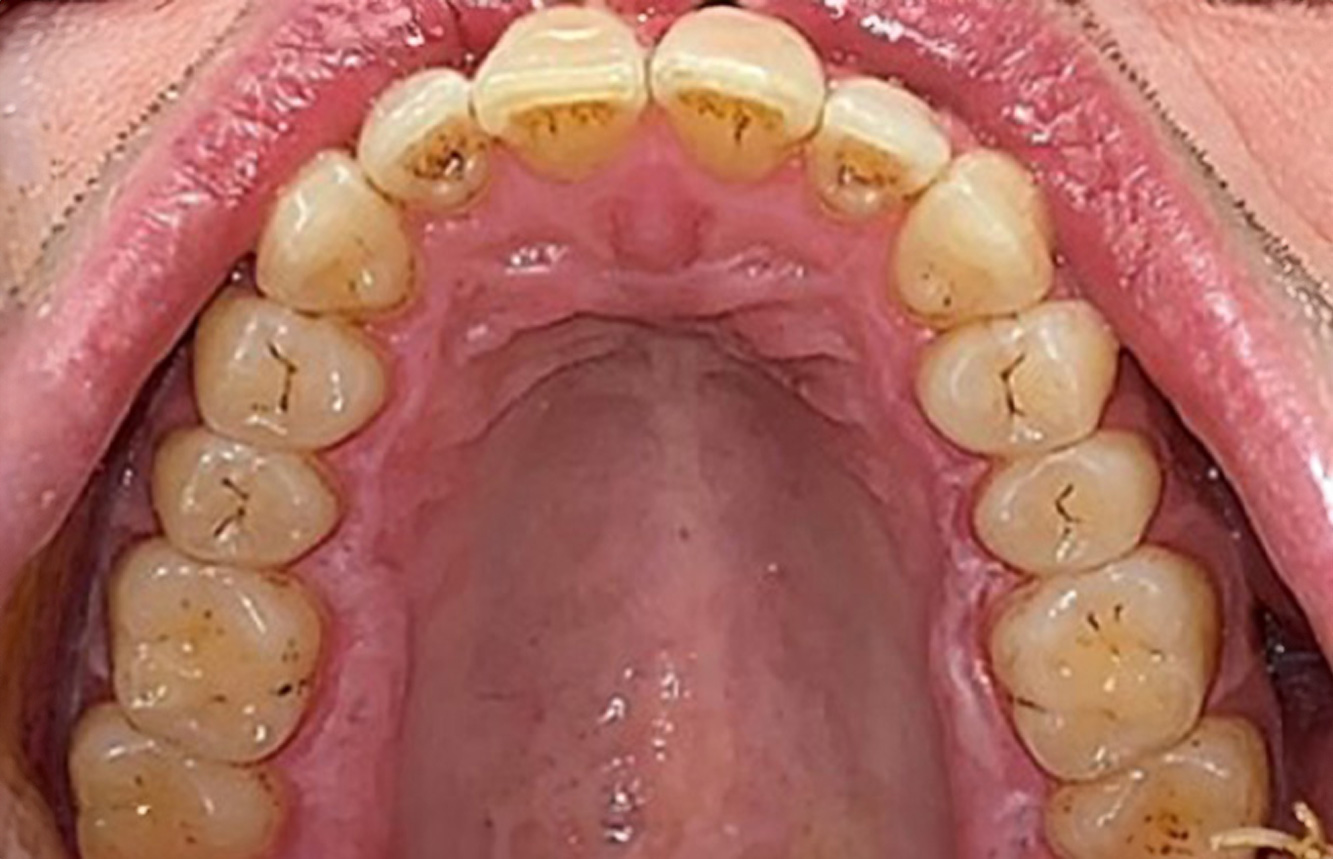

Patientenfälle nach IPCUm das Zusammenspiel der für den IPC definierten Bedarfs- und Risikofaktoren sowie die Auswirkungen einzelner Faktoren zu illustrieren, dienen nachstehende Fallbeispiele*. Die mundgesunde DiabetikerinEine 51-jährige mundgesunde Diabetikerin stellt sich zur Präventionssitzung vor. Die Blutzuckerwerte sind stabil bei einem HbA1c = 6,2%, folglich gilt sie mit dem entsprechenden Medikament Metformin (Antidiabetikum) als suffizient eingestellt. Die Patientin hat keine bestehenden Versorgungen oder orale Vorerkrankungen. Anhand der aktuellen Befunde lässt sich eine Gingivitis bei sonst stabilem parodontalem Zustand (Stage II, Grad B) feststellen. mehr Infos Fallpräsentation: Management komplexer ZahnprothetikEs ist längst bekannt, dass Mundgesundheit und Allgemeingesundheit in direktem Zusammenhang stehen und einen zum Teil bidirektionalen Einfluss aufeinander haben. Die Berücksichtigung beider Faktoren sind bei der Planung der oralen Prävention und Therapie der Patienten in der Zahnarztpraxis unabdingbar. Dabei ist oberstes Ziel, die Gesundheit und die Lebensqualität der Patienten sowohl aus zahnmedizinischer -und medizinischer Sicht zu erhalten. mehr Infos Der (mund)-gesunde Patient mit ImplantatenDer 55-jährige Patient gibt in der Anamnese an, keine Allgemeinerkrankungen zu haben und keine Medikamente einzunehmen. Die Lebensgewohnheiten des Patienten sind ebenfalls unauffällig. Der Patient hat einige zahnärztliche Restaurationen und zwei Implantate (2. und 4. Quadrant). Anhand der aktuellen Befunde lässt sich eine Gingivitis bei stabilem parodontalen Zustand am reduzierten Parodont (Stadium III, Grad A) feststellen. mehr Infos Der gesunde Patient mit parodontaler Vorerkrankung & PeriimplantitisEin 52-jähriger Patient stellt sich zur Präventionssitzung vor. Der Patient hat keine Allgemeinerkrankungen und nimmt keine Medikamente ein. Er hat verschiedene zahnärztliche Versorgungen und zudem zwei aktive kariöse Läsionen. Außerdem verfügt der Patient über vier Implantate (2., 3. und 4. Quadrant). Es zeigt sich eine parodontale Vorerkrankung (Stadium IV, Grad B). Derzeit herrschen stabile parodontale Verhältnisse, lediglich am Implantat regio 36 zeigen sich Sondierungstiefen (ST) von 5 mm. Zudem lässt sich eine Gingivitis feststellen. mehr Infos Der Diabetiker mit ParodontitisDieser Fallbericht eines 52-jährigen Mannes mit Typ-2-Diabetes und Parodontitis hebt hervor, wie durch individuelle Vorsorgemaßnahmen, die Gesundheit des Zahnhalteapparates erhalten bzw. das Fortschreiten der Erkrankung kontrolliert werden kann. mehr Infos Der 28-jährige Raucher mit ZahnerosionenDieser Fallbericht eines 28-jährigen Rauchers mit Zahnerosionen zeigt die Bedeutung personalisierter Patientenprofile. Er unterstreicht die Notwendigkeit, sowohl die Mundgesundheit als auch die allgemeine Gesundheit zu berücksichtigen, um Erkrankungen der Zähne bzw. des Zahnhalteapparates effektiv zu verhindern. mehr Infos Der Endokarditis-Patient mit aktiven KariesläsionenDer Patient ist 39 Jahre mit Z.n. Herzklappenersatz wegen Klappenfehlers und Endokarditis. Als Antikoagulans (Gerinnungshemmer) wird regelmäßig ASS 100 eingenommen. Aus dem Bereich Lebensstil ist die Ernährungsweise als kariesfördernd einzustufen, da mit hoher Regelmäßigkeit zuckerhaltige Lebensmittel sowie sechs bis sieben Mahlzeiten täglich verzehrt werden. Die Mundgesundheit des Patienten zeigt ein mittleres Kariesrisiko mit aktiven Läsionen. Das Parodontitisrisiko ist niedrig, es besteht eine Gingivitis. Es ergeben sich folgende Empfehlungen für die Prophylaxebehandlung. mehr Infos Die gesunde Patientin mit parodontaler VorerkrankungDie 68-jährige Patientin hat keine zahnmedizinisch relevanten allgemeingesundheitlichen Vorerkrankungen oder Medikation, auch aus dem Lebensstil ergibt sich kein besonderes Risiko. Die Patientin hat zwei Implantate (3. Quadrant, seit fünf Jahren) sowie eine parodontale Vorerkrankung (Parodontitis Stadium IV, Grad B) mit Zahnverlust. Derzeit zeigen sich stabile parodontale Verhältnisse. Für die Prophylaxesitzung ergeben sich vier Empfehlungen in den Bereichen Anamnese/Befund, Motivation/Instruktion, der Wahl der geeigneten Instrumente und für Resümee/Folgetermin. mehr Infos